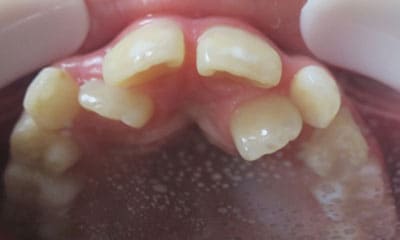

● 先天性の萌出方向異常を部分矯正で治療

藤沢デンタルオフィスの虫歯や破折で先天性の萌出方向異常を部分矯正で治療

01

02

03

04

05

06